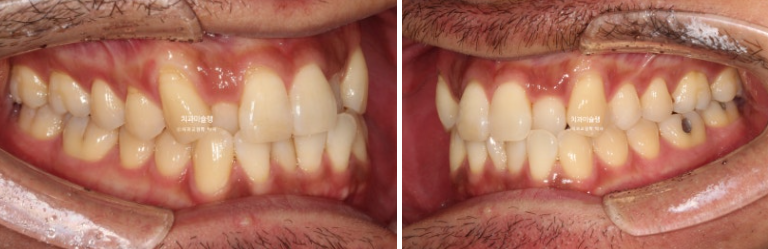

덧니가 있고 위아래 치아 중심선이 어긋나 있습니다.

치아중심선이 어긋나 있는 것은 아래턱 비대칭이 있기 때문입니다.

그에 비해 뒤쪽 어금니 교합은 좋은 편 입니다.

환자분의 얇은 입술과 입매를 고려하면 작은어금니 발치교정은 하지 않는 것이 좋은 상황이라 비발치 교정을 결정합니다.

그러나 사랑니 공간이 없는 상황이라 비발치 후방이동 방법은 쓰기 어렵습니다.

따라서 상악 악궁확장장치를 통해 덧니를 해결하기로 합니다.